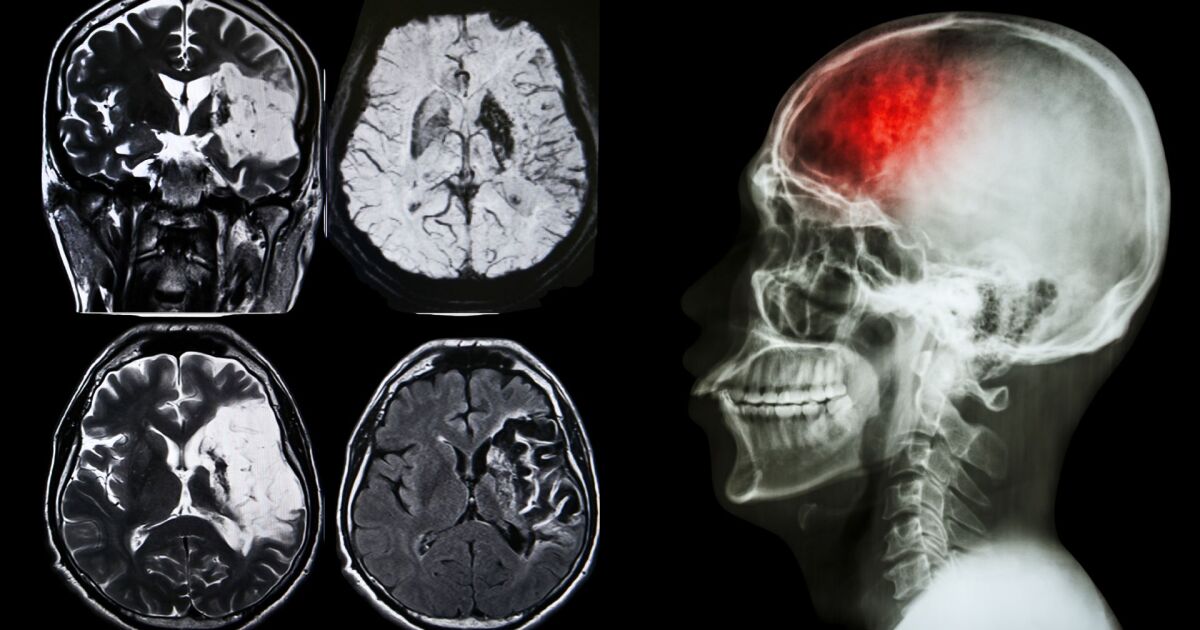

Основателят на БДИ доц. Росен Калпачки представи обнадеждаващи данни за развитието на лечението на инсулт в страната. Въпреки че на фона на европейската цел от 15% постигнатите 4% може да изглеждат скромно, той подчертава, че напредъка е съществено.

За десетилетието от 2014 до 2024 г. броят на тромболизите в България се е увеличил драматично, от 270 годишно на близо 2000, представлявайки 7-8-кратен ръст. Тромболизата е ключова част от съвременното лечение на исхемичния инсулт и постепенно се налага като стандарт във все повече медицински центрове.

Ситуацията с тромбектомията е още по-тревожна - едва 0,3% от исхемичните инсулти се лекуват по този начин, въпреки че това е важна алтернатива за определени случаи.

България заема третото място по заболеваемост и смъртност от мозъчен инсулт в Европа, което подчертава сериозността на проблема в национален мащаб.